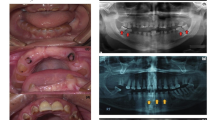

(A) Pedigree of the family where SLC24A4 variant c.1192C > T segregates in an autosomal recessive fashion. The asterisks show tested individuals. The red arrow indicates the index patient, who was subjected toexome sequencing. T shows the disease-allele while C is the wild-type presentation (B) The representation of amelogenesis imperfecta in the patients. (i), (ii), and (iii) are the clinical features of patient IV-4 showing yellow-brown discoloration, (iv) Orthopantomogram (OPG) of the patient IV-4 showing thin layer of enamel, high radio-density and distinction from the dentin, while (v) and (vi) are the clinical photographs of the patient IV-5 showing creamy type of discoloration, attrition and dental caries

For clinical and radiological investigations, a 35-years old patient (IV-4) was referred to Khyber Medical College of Dentistry, Peshawar, Khyber Pakhtunkhwa, Pakistan. His major complaints were yellow-brown staining, eating, and chewing difficulties of all the teeth (Fig. 1B-i,ii,iii). The patient presented no complications of other body organs during the clinical evaluation. The Orthopantomogramm (OPG) of this patient showed a thin (hypoplastic) mandible with missing posterior teeth on the right side and carious molars with a periapical infection on the left side. The maxilla showed impacted canine in the right premolar region with a missing molar and spacing among the dentition on the right side of the arch.

Additionally, the teeth showed generalized horizontal bone loss, more prominent around the maxillary molars. OPG also showed the presence of a thin layer of enamel, especially in the region of molars of the upper jaw. Furthermore, enamel appeared to have higher radio-density compared to the dentin. Moreover, the dentin appeared normal and distinct from the enamel (Fig. 1B-iv).

Patient IV-5, the 27-year old brother of patient IV-4, presented with creamy discoloration and attrition of the frontal maxillary teeth while dental caries in the mandibular premolars and molars (Fig. 1B-v,vi).